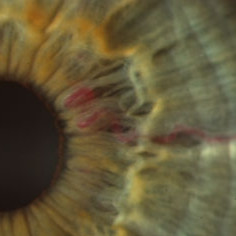

Iris neovascularization

Iris neovascularization secondary to a medium-sized choroidal melanoma with a long-standing exudative retinal detachment (prior to treatment).